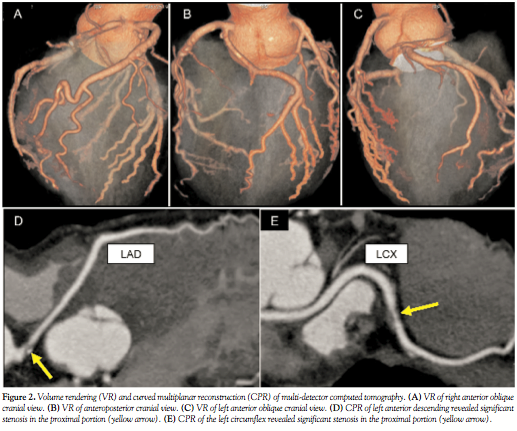

The left anterior descending artery (LAD) branched off the proximal right coronary artery (RCA) and flowed through the anterior aorta. The left circumflex coronary artery (LCX) arose from the separate ostium in the right coronary cusp and flowed through between the aorta and the pulmonary artery, and the posterior aorta. Figure 2 shows the volume rendering (VR) view and the curved multiplanar reconstruction (CPR) views of the MDCT. VR view of the left coronary artery (LCA) revealed only an intermediate ramus and a diagonal branch, without main branches of the LAD and the LCX. Indeed, VR views revealed that the RCA included the anomalous origin of the LAD from the proximal RCA, and that the LCX arose from the separate ostium in the posterior right coronary cusp (RCC). CPR views revealed significant atherosclerotic lesions in the proximal segment of the LAD and the middle segment of the LCX.